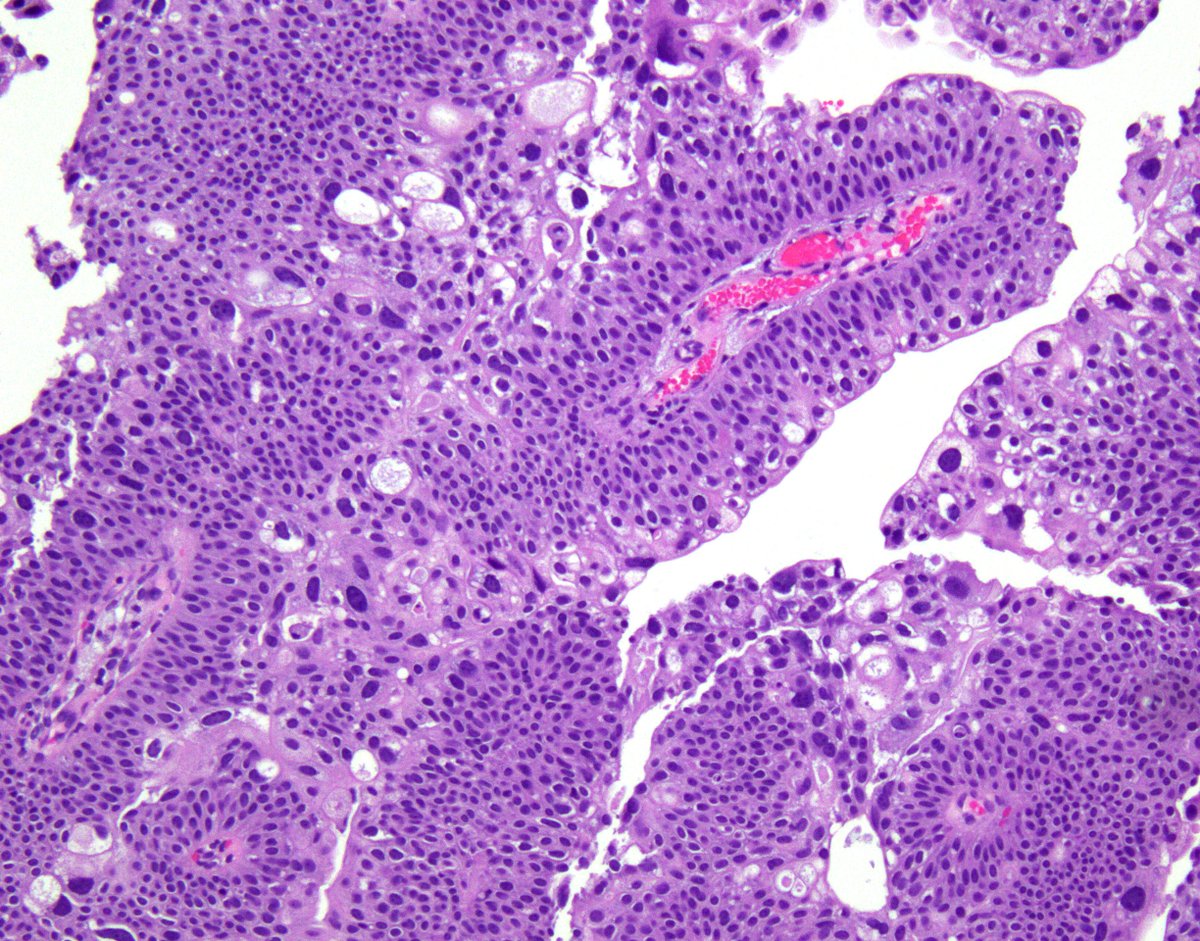

👉 41 YO male with history of renal transplant. Histology provided from the native kidney. What is your diagnosis? #PathTwitter #GUpath #Surgpath #Pathology #Pathresidents #renalpath